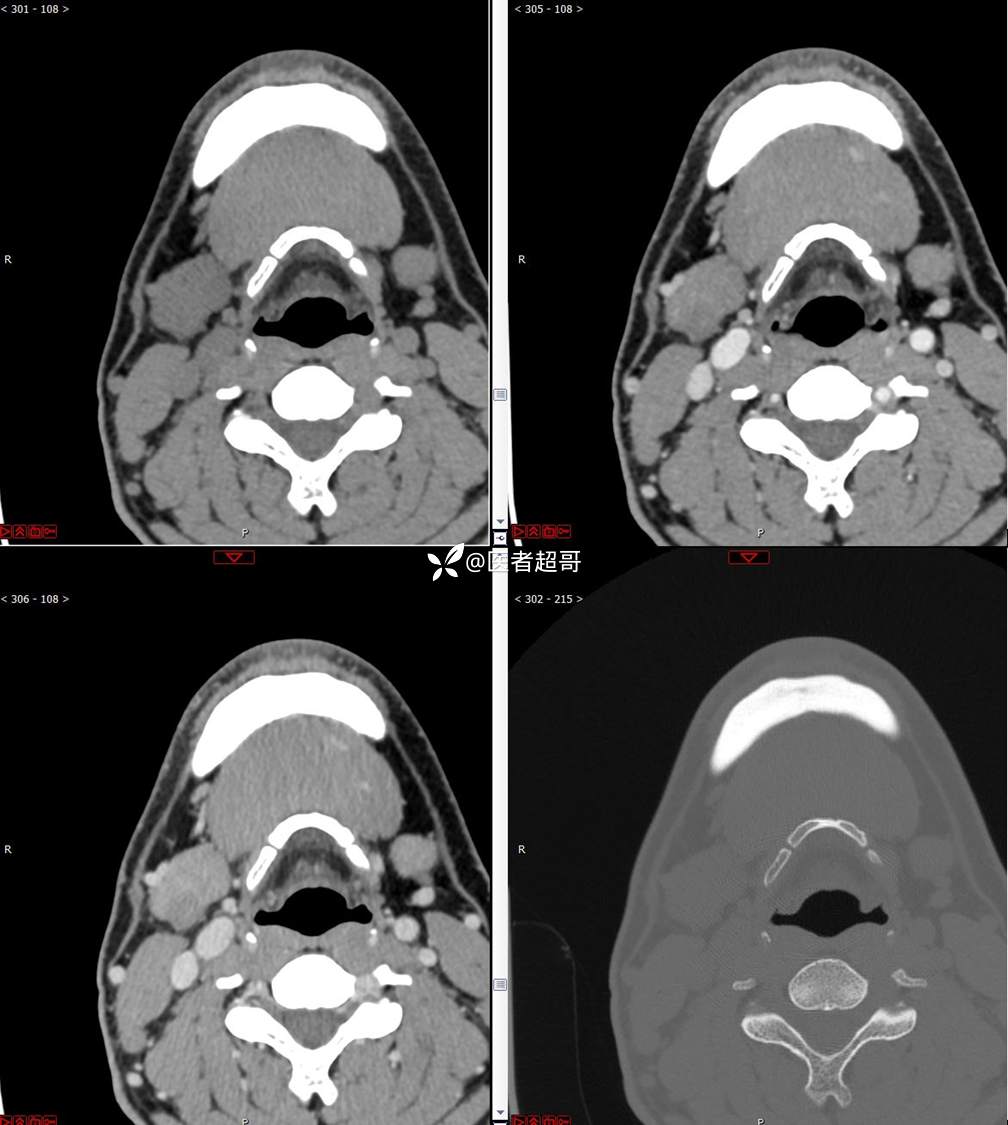

颌下腺结节:青年男性,颌下区无痛性肿物,请分析~~~

主 诉:发现右颌下区无痛性肿物1年。

现病史:患者于1年前发现右颌下区一肿物,肿物约“葡萄粒”大小,无疼痛不适,无进食时颌下区肿胀及疼痛不适。2023-10-1就诊于市中医院行超声检查;未予治疗。肿物体积无明显变化,求进一步治疗就诊于我院门诊,门诊以“颌下肿物”收入我科。患者自发病以来,神志清,精神佳,食欲好,睡眠好,大小便正常,近期体重无明显变化。